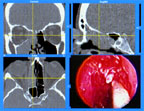

Surgeons performing minimally invasive surgery can now use Visualization Technology's InstaTrak® System for image-guided surgery to see surrounding anatomy during surgery and operate more precisely. InstaTrak uses Parallax Graphics' XVideo Xtra video card to bring high-quality digital video from the endoscope into the workstation for display and computer-aided vision.

Surgeons use VTI's InstaTrak System to see surrounding anatomy

during minimally-invasive surgery.

InstaTrak gives a three-dimensional "road map" to surgeons, so that they can see not only the area at the tip of the endoscope, but also the surrounding anatomy and where their surgical instruments are. Now the surgeon can see where the optic nerve lies and where the surgical instrument is in relationship to it. This computer-aided vision gives surgeons the ability to operate with greater precision, benefiting their patients.

The InstaTrak display gives a 3D "road map" to surgeons by showing CT

cross sections and live video from the tip of the endoscope.

InstaTrak uses CT scans acquired before the operation to provide the three-dimensional "road map." Patients wear a special head-set while the CT scans are taken and during the operation, so that the image data can be aligned precisely with the patientąs orientation. Before the operation, sensors are attached to the surgical instrument so that its location is tracked precisely. Endoscopic video data is also integrated in the computer system so that the surgeon can see all of the important data on screen at once.